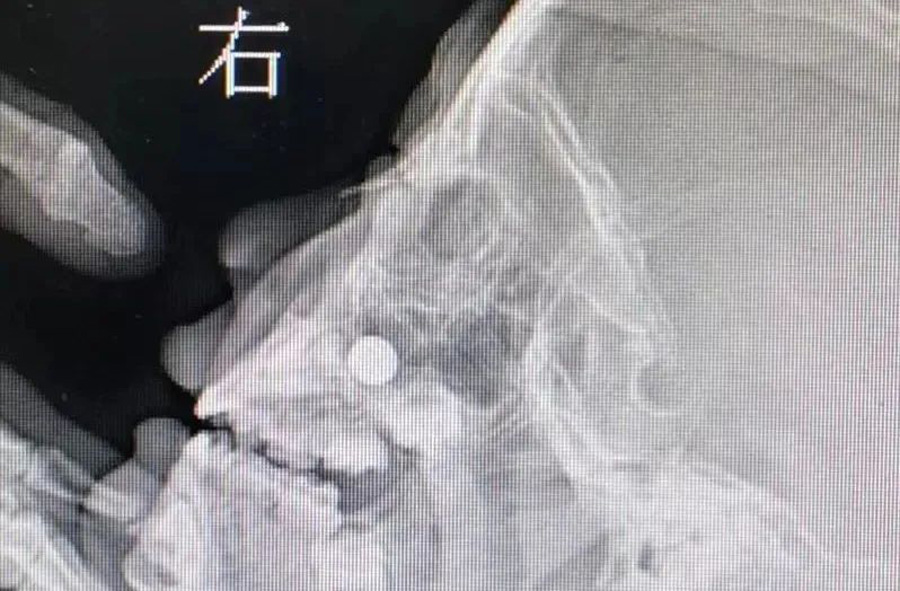

3月23日,120急救车将1名患儿送至蜜桃视频 。患儿3岁,来时明显看出鼻子不舒服。妈妈说,前一天儿子把纽扣电池塞右侧鼻子里了,但在当地医院没取出来。如果真的是纽扣电池,那就危险了,因为电池产生的腐蚀性物质及微电流会造成鼻腔黏膜腐蚀伤,甚至后期可能出现鼻中隔穿孔。门诊医生接诊后,未能看到鼻道中有明显异物,耳鼻喉科开放急危重症绿色通道。由于患儿及家长核酸结果未回报,耳鼻喉科医生在三级防护下做了鼻咽镜检查。在患儿下鼻道底部,发现有黏膜肿胀以及典型的纽扣电池异物放电导致的“冒泡”现象,但异物被肿胀的黏膜包裹,大小及形态显示不清。鼻咽部平片同样显示鼻腔底部有圆形金属异物。

由于异物位置特殊,以及患儿不配合,门诊不能顺利取出异物,急诊全麻取出是最好的办法。在全麻下,耳鼻喉科副主任李莉萍经过20多分钟定位、钩取,才将异物取出来。取出的纽扣电池颜色发黑,患儿右侧鼻腔黏膜也已被腐蚀成了黑褐色。经过给药处置、鼻腔消炎等治疗,第三天患儿出院回家了,后期需定期复查。